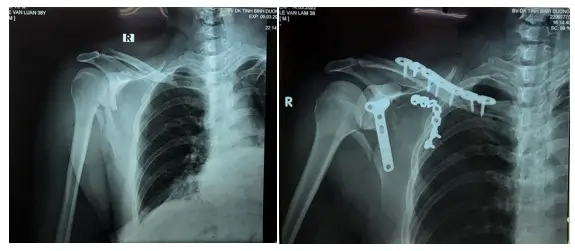

Gãy xương bã vai+gãy xương đòn, kết hợp xương nẹp vit